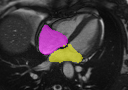

Multi-view segmentation.

The competence of our model to perform end-to-end segmentation across all planes is shown in Table 2 and Fig. 3. Our model not only exhibits comparable quantitative dice scores with nnUNet (that leverages exhaustive parameters tuning) but also shows superior performance over UNETR+ in all regions for both SA/LA planes. This benefit is gained from the learned whole-heart representation. Moreover, the superior performance against SA-only and LA-only segmentation also highlights the significance of integrating multi-view CMR information for more accurate segmentation outcomes.

GTnnUNetUNETR+Ours SA/LA onlyOurs AllRefer to captionRefer to captionRefer to captionRefer to captionRefer to captionRefer to captionRefer to captionRefer to captionRefer to captionRefer to captionRefer to captionRefer to captionRefer to captionRefer to captionRefer to caption

Figure 3: Qualitative segmentation results among nnUNet, UNETR+, and the proposed methods. UNETR+ and the proposed approach in the last column (Ours All) use all sparse CMR sequences as network input, while nnUNet and the second last column (Ours SA/LA) are trained solely with either SA or LA views.